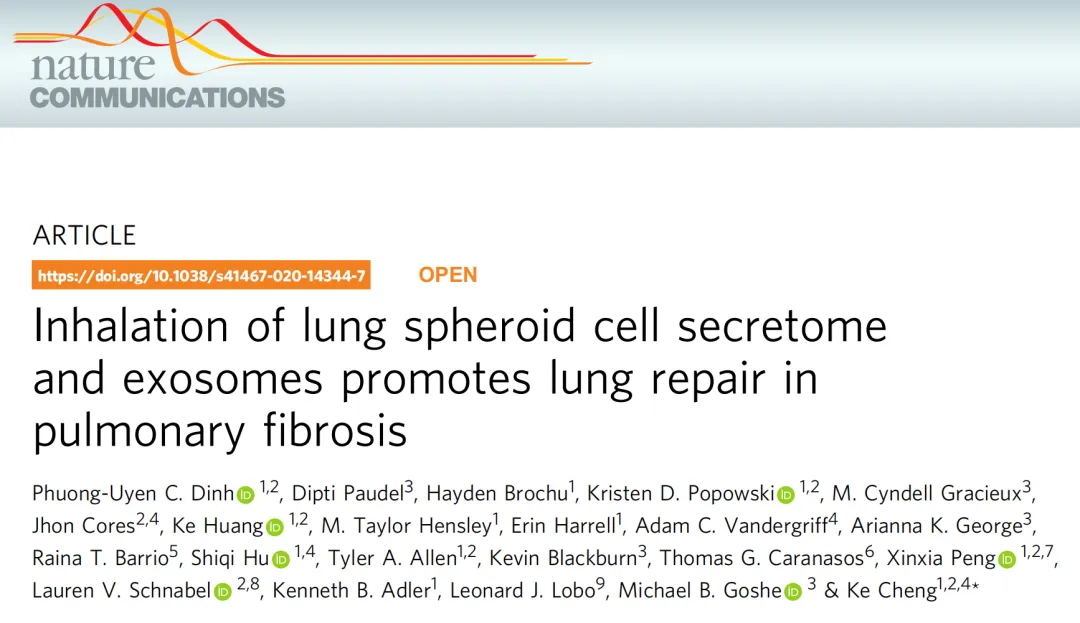

研究显示,自体肺干细胞分泌组雾化吸入后,小鼠肺纤维化面积减50%,效果显著优于传统的脐带间充质干细胞;

海南医学院的临床研究中,自体脐带间充质干细胞外泌体雾化治疗肺纤维化患者,早期干预组病灶吸收时间缩短40%。